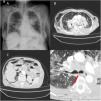

(A) Plain chest X-ray with left parahilar mass and interstitial pattern consistent with bilateral lymphangitis. Significant subcutaneous emphysema can be observed at the cervical and costal level. Pneumomediastinum is also identified around the cardiac silhouette and pneumoperitoneum in the right hemidiaphragm. (B) Computed tomography of the chest (lung window) showing pneumomediastinum, pneumopericardium, and subcutaneous emphysema, in addition to the previously identified tumors and left pleural effusion. (C) Computed tomography of the abdomen (lung window) showing pneumoperitoneum, retropneumoperitoneum, and subcutaneous emphysema. (D) Computed tomography of the chest (lung window) showing a fistula in the posterior wall of the right main bronchus (arrow).

We report the case of a 79-year-old woman diagnosed 1 month before the current episode with stage IVB cancer of the left lung (cT4N3M1c) with bilateral pulmonary carcinomatous lymphangitis, multiple brain lesions, and T12 metastatic bone disease. The diagnosis had been made by endobronchial ultrasound, with aspiration of the lung mass in the left upper lobe at 11L, with no subsequent complications. Histology was consistent with non-small cell carcinoma with EGFR mutation. The patient was awaiting chemotherapy and radiation therapy. She was admitted for general deterioration associated with urinary sepsis, with no dyspnea, chest pain, respiratory symptoms, or recent trauma. Physical examination and vital signs were normal. Labs showed leukocytosis (18,740/μL) with elevated acute phase reactants (CRP 365mg/L, PCT 9.63ng/mL) and pathological urine with nitrites and abundant bacteriuria. The chest X-ray was unchanged from the previous test. Treatment started with antibiotics and fluid therapy with good progress, but on the third day of admission, she developed subcutaneous thoracic-abdominal and cervical crepitations consistent with subcutaneous emphysema, which was confirmed on a new X-ray (Fig. 1A). A thoracic-abdominal computed tomography scan was requested, which showed severe subcutaneous emphysema from the cervical to the pelvic region, combining extensive pneumomediastinum and, to a lesser extent, pneumopericardium (Fig. 1B), as well as significant pneumoperitoneum and retropneumoperitoneum (Fig. 1C). A fistula was also seen in the posterior wall of the right main bronchus, but it was not possible to confirm that it communicated with another organ (trachea or esophagus) or only with the mediastinum. Given the underlying situation of the patient, fiberoptic bronchoscopy was not performed to confirm the presence of the fistula, although the previous endobronchial ultrasound had not shown any lesions in the right bronchus, nor was a biopsy performed in this region. In the following 72h, despite laboratory improvement, the patient presented progressive respiratory deterioration and finally died.